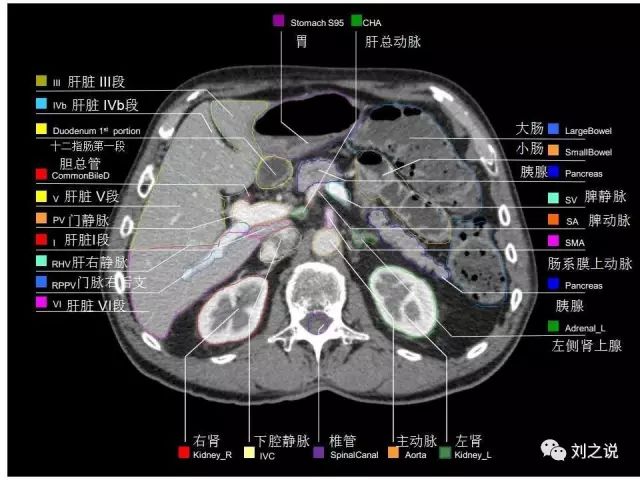

参考RTOG共识和3D-body解剖。

来源:刘之说